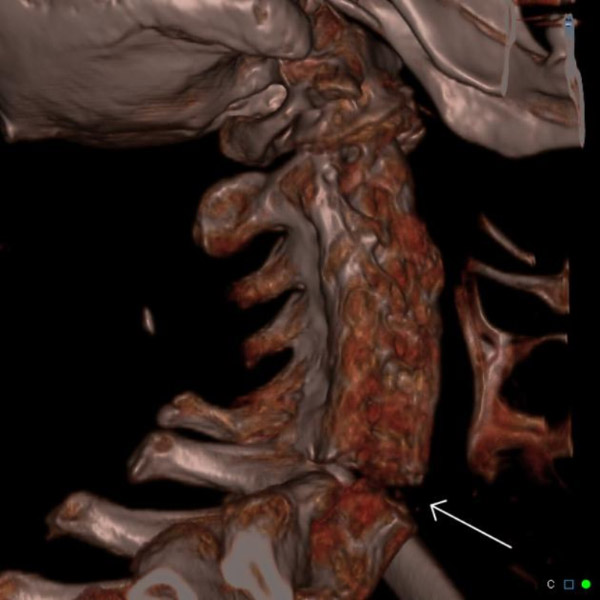

Chụp cắt lớp vi tính (CT) sử dụng kết hợp tia X và công nghệ máy vi tính để tạo ra hình ảnh chi tiết về cấu trúc bên trong cơ thể. Khác với chụp X-quang chỉ tạo ra hình ảnh hai chiều, chụp CT khớp có thể chụp ảnh không chỉ cấu trúc xương mà còn cả các mô mềm như gân, dây chằng, cơ và mạch máu. Điều này cho phép phân tích toàn diện tình trạng của khớp đang được kiểm tra, bao gồm cả tổn thương sụn.

Trong quá trình chụp CT, một chùm tia X hẹp được phát ra từ máy quét và di chuyển xoay tròn xung quanh cơ thể. Các cảm biến sẽ ghi nhận lượng tia X được hấp thụ bởi các mô khác nhau, từ đó tạo ra hình ảnh chi tiết về cấu trúc bên trong. Thông tin này sau đó được xử lý bởi máy vi tính để tạo ra hình ảnh hai chiều hoặc ba chiều, giúp bác sĩ có cái nhìn trực quan về cấu trúc khớp.